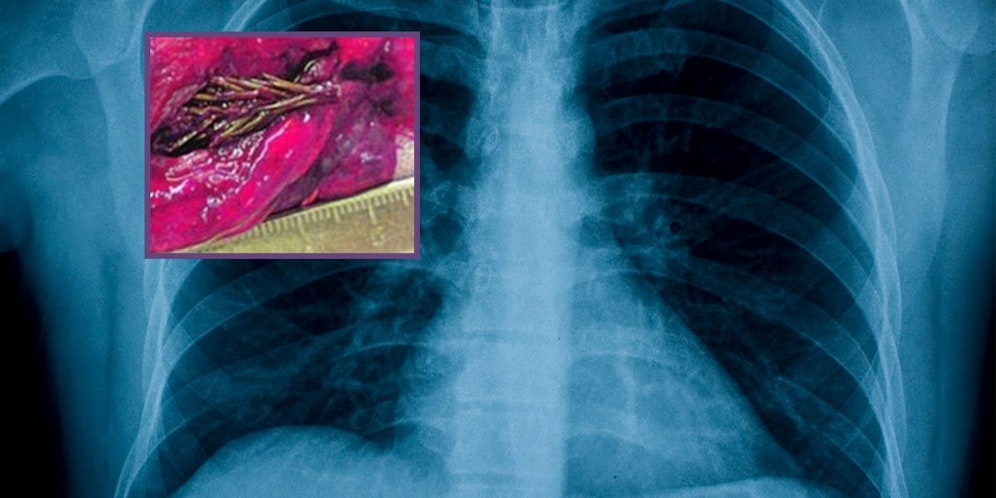

Ärzte im Ural in Russland machten während einer Lungenoperation eine unglaubliche Entdeckung. Nachdem der 28-jährige Artyom Sidorkin über extreme Brustschmerzen und Bluthusten geklagt hatte, wurden – wie es state of the art ist – Röntgenaufnahmen gemacht. "Wir fanden etwas, das genau wie ein Tumor aussah. Wir waren uns zu 100 Prozent sicher", sagte der Chirurg, Vladimir Kamashev, aus Izhevsk. "Ich hatte schon Hunderte gesehen, also entschieden wir uns für eine Operation."

Tanne statt Tumor

Bevor der Chirurg den größten Teil der Lunge des Mannes entfernte, untersuchte er das bei einer Biopsie entnommene Gewebe und konnte nicht glauben, was er sah: eine kleine Tanne. "Ich dachte, ich hätte Halluzinationen", sagte Kamashev. "Ich bat meinen Assistenten, einen Blick darauf zu werfen, er nickte schockiert."

Samen eingeatmet

Es ist anzunehmen, dass der Patient irgendwie einen Samen eingeatmet hat, der später in seiner Lunge zu einer kleinen Tanne heranwuchs. Der Bluthusten könnte von den winzigen Tannennadeln verursacht worden sein, die die Blutkapillaren durchstochen hatten. "Es war sehr schmerzhaft. Aber um ehrlich zu sein, habe ich keinen Fremdkörper in mir gespürt", so der Patient." Ich bin so erleichtert, dass es kein Krebs ist."